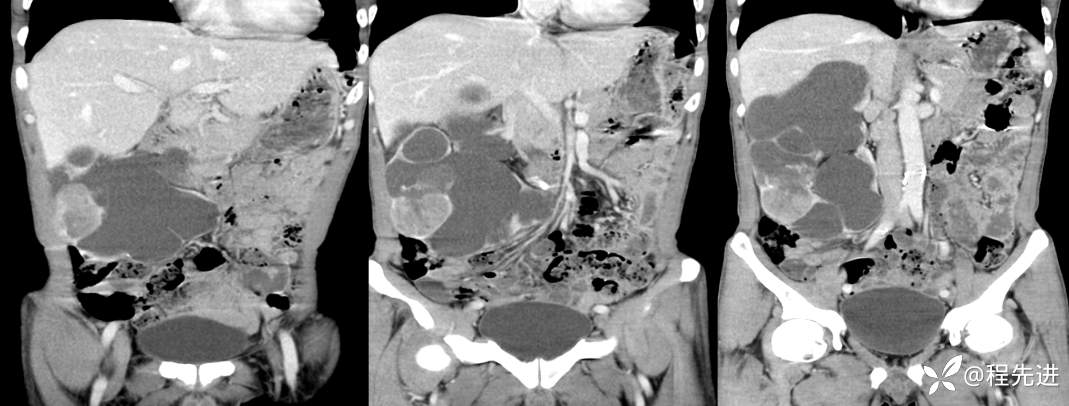

CT平扫+增强

左平扫,右增强

来张特定(左平扫,中动脉期,右静脉期)